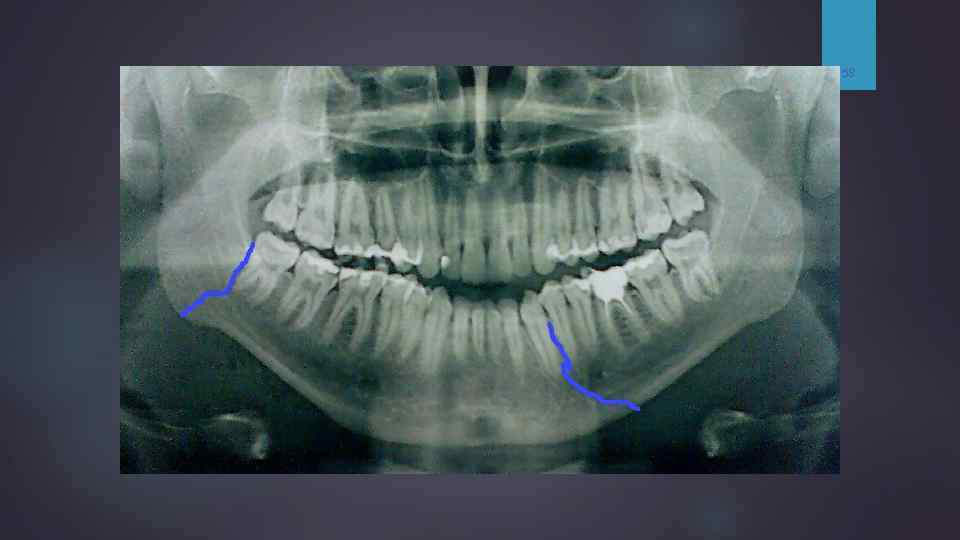

Ортопантомограмма. Двусторонний перелом тела нижней челюсти — линия перелома справа проходит между 6 и 5, слева — в области угла. Отломок смещен вертикально.

58